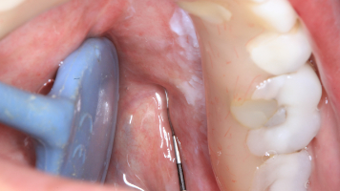

Second North American Dental Hygiene Research Conference Getting